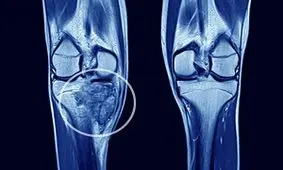

سرطان استخوان نوع نادری از سرطان است که از استخوانها شروع میشود.

بیماری سرطان استخوان از زمان تکثیر سلولهای استخوانی به سرعت رشد کرده و شروع به تجزیه کردن استخوان میکند.

سرطان استخوان یک بیماری نادر است و یک درصد از تمام انواع سرطان را تشکیل می دهد و تومورهای استخوانی غیر سرطانی به مراتب شایعتر از تومورهای سرطانی هستند.